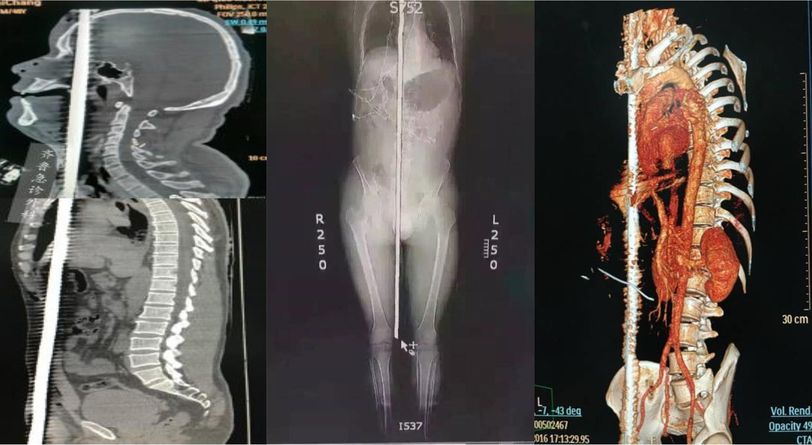

Construction workers are predisposed to array of hazards due to unsafe working conditions. Accidents at construction sites are attributed to falls, resulting in trauma, disability, and sometimes, death. One such fall resulted in complex presentation of rebar penetrating trauma when a 47 years old unidentified, male construction site worker fell from an altitude of 5 m, and landed on erect rebar, resulting in combined penetrating trauma of head, neck, chest, abdomen, pelvis and scrotum. Radiography showed brain and cardiac contusions, subarachnoid hemorrhage, lung injury along with pneumothorax and mediastinal emphysema, injuries to tongue, palate, and right lobe of thyroid. Despite of severity of trauma, timely first response, efficient triage by emergency nurses, multidisciplinary surgical approach and psychological support resulted in phenomenal recovery within 2 months. Follow up at 5 and 11 months showed tremendous improvement. Sources: o Zhang M, He Q, Wang Y, Pang S, Wang W, Wang D et al. Combined penetrating trauma of the head, neck, chest, abdomen and scrotum caused by falling from a high altitude: A case report and literature review. International Emergency Nursing. 2019;44:1-7. o Douglas KE, Adeloye FT. Pattern of accidents in building construction sites in Obio Akpor Local Government Area of Rivers State, Nigeria. Niger J Med. 2016 Jul-Sep;25(3):234-53. PMID: 30011168.